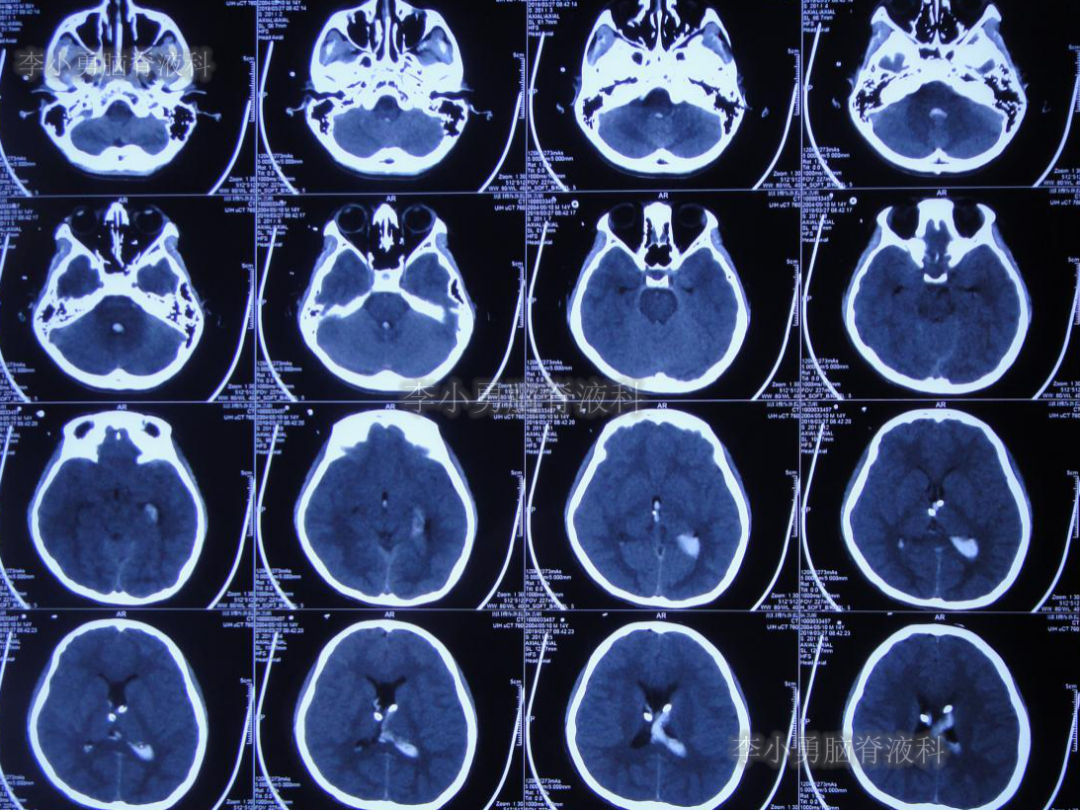

2019年3月26日患者突发头痛及呕吐,随后出现晕厥。急救车送至河南省周口市某医院。行头颅CT(图-1):脑室内出血,次日急诊给予行双侧脑室外引流术(图-2)(第一次的脑室外引流术)。

图-1:2019年3月26日头颅CT:脑室内出血

图-2:2019年3月27日头颅CT:双侧脑室外引流术后